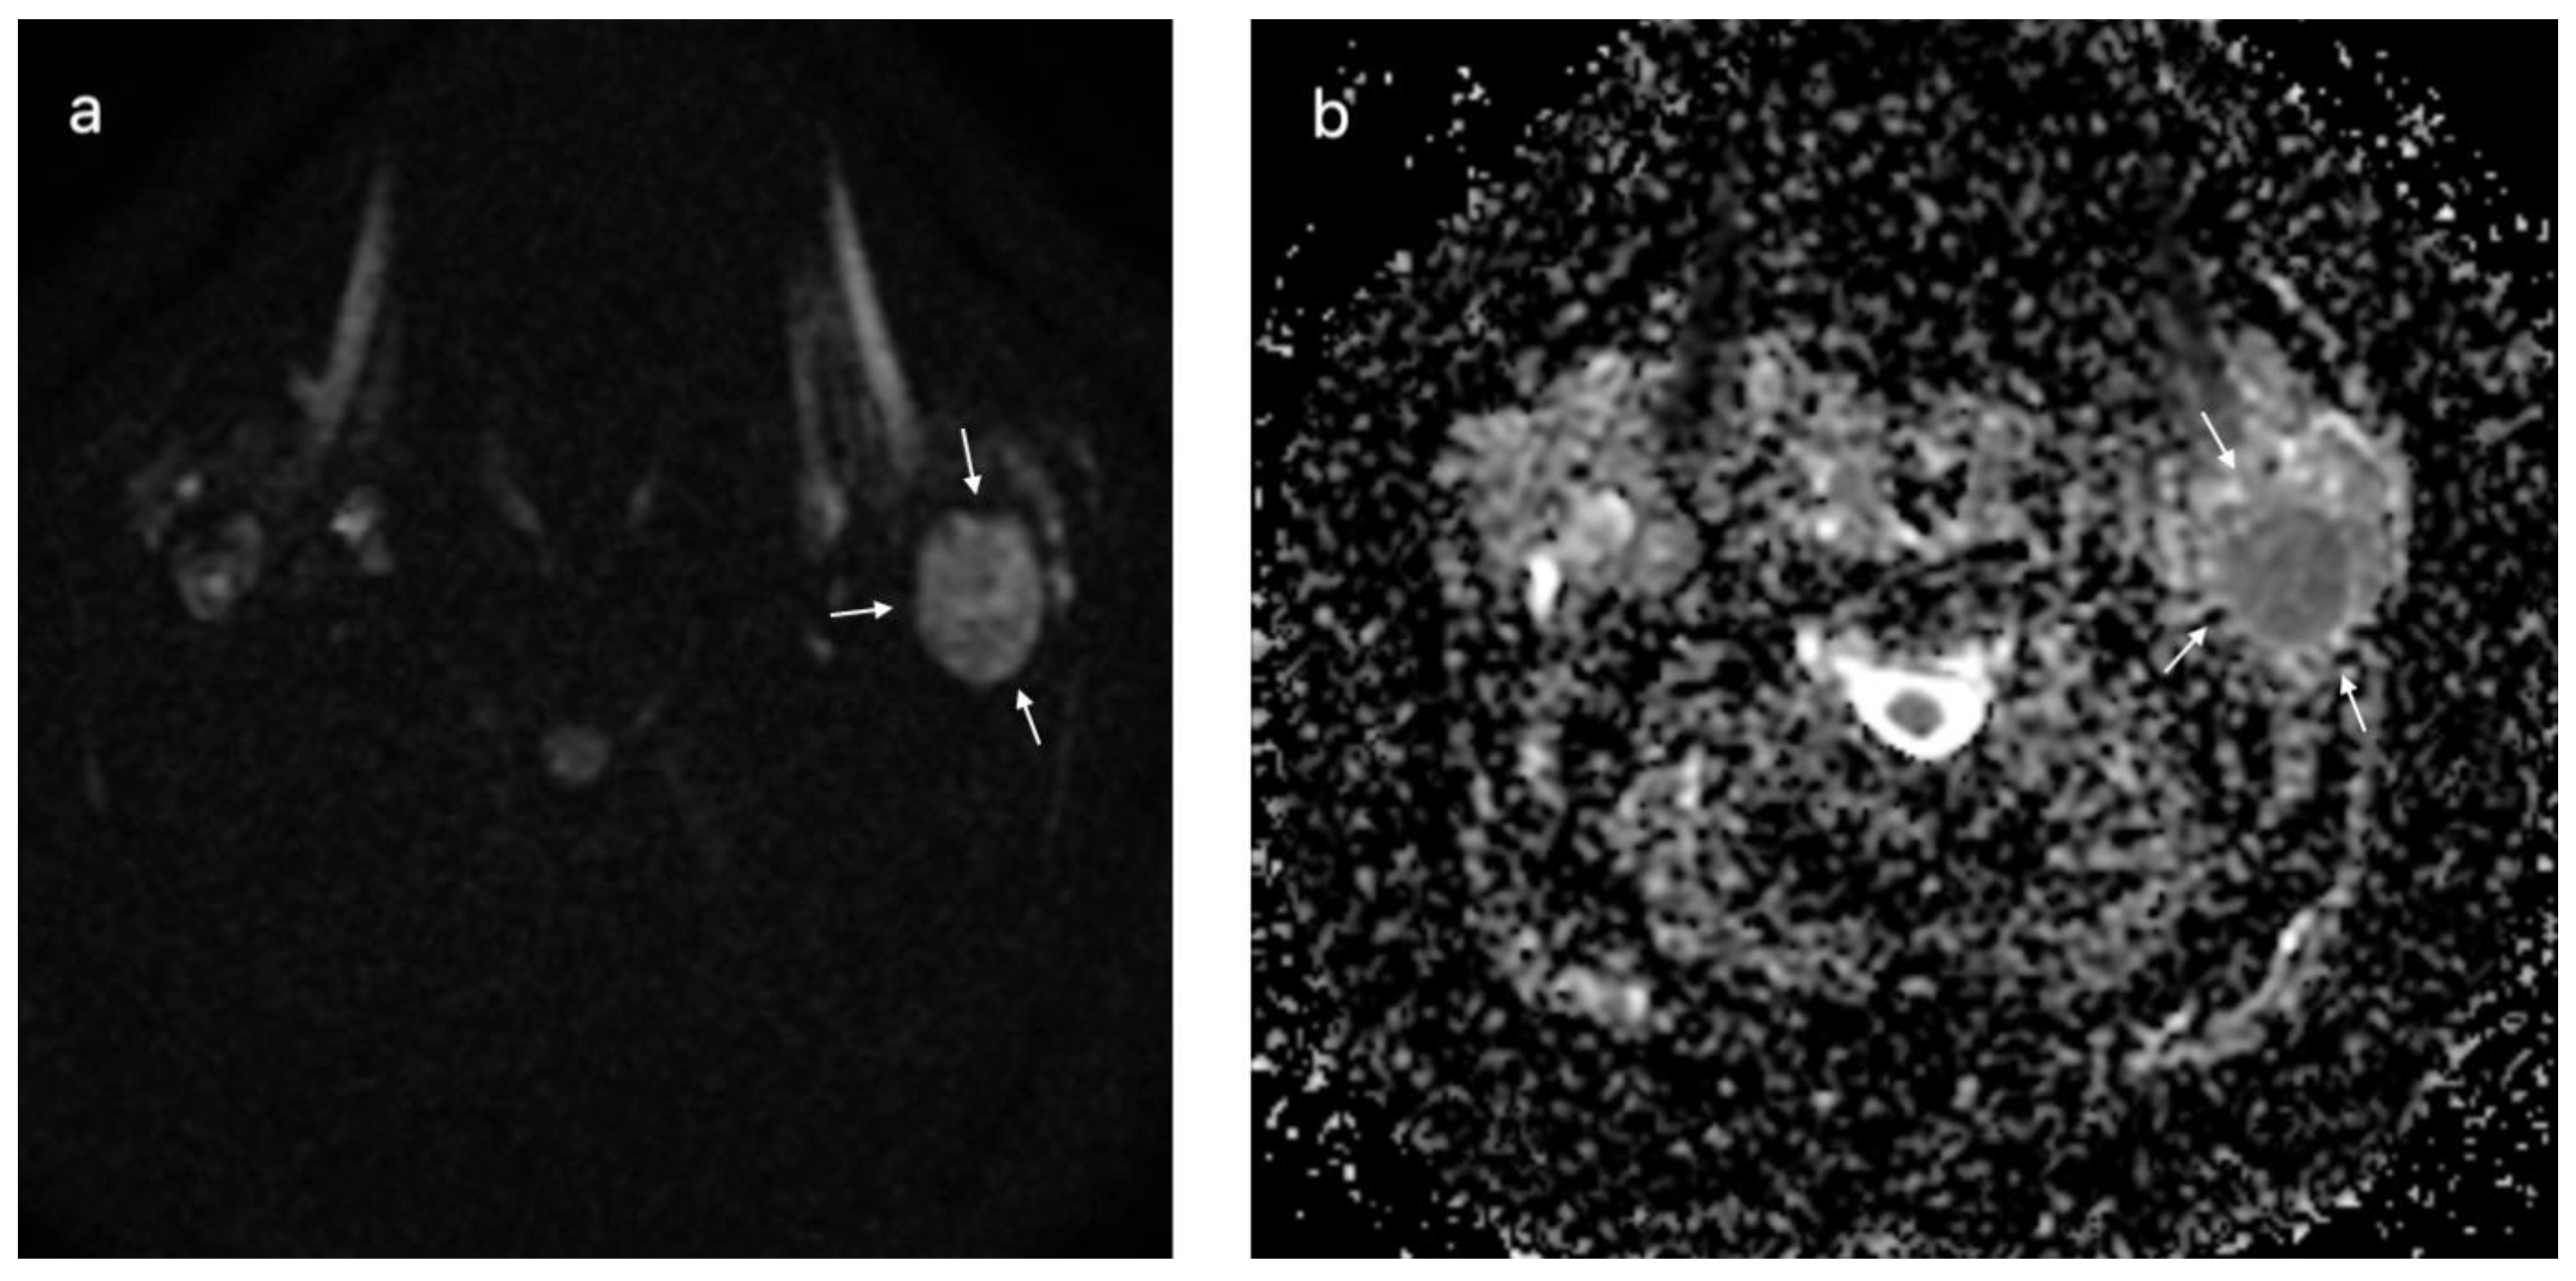

| DWI MRI, ADC × 10−3 mm2/s, median (IQR) | 1.03 (0.8–1.44) | 0.78 (0.68–0.99) | 0.024 |

| DWI MRI, ADC × 10−3 mm2/s, median (IQR) | 1.5 (1.25–2.1) | 0.86 (0.73–1) | <0.001 |